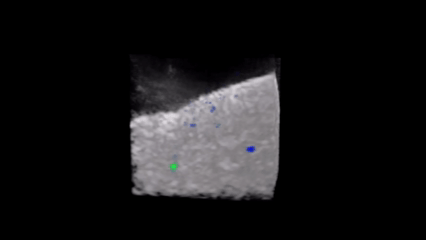

Densités de probabilité de présence de deux sphères métalliques enfouies dans une suspension granulaire ultra-diffusante superposées à une image échographique (noir et blanc) totalement brouillée. Chaque couleur correspond à un diamètre de sphère différent: 10 mm (bleu) et 8 mm (vert). Crédit image : Arthur Le Ber

L’idée des chercheurs [1] est d’exploiter les corrélations entre la matrice mesurée dans le brouillard et l’empreinte de référence. Ces corrélations permettent d’isoler les contributions spécifiques de la cible et de la faire apparaître, avec une précision meilleure que la longueur d’onde utilisée. Au lieu de corriger les effets du désordre – une tâche pratiquement impossible dans les milieux opaques –, la méthode révèle ce qui, dans le signal, résiste au brouillage. Pour valider ce principe, l’équipe a mené plusieurs expériences en acoustique ultrasonore. Des sphères métalliques enfouies dans une suspension granulaire, totalement invisibles par échographie conventionnelle, ont pu être localisées avec une fiabilité quasi certaine. Dans un second test, la méthode a permis de détecter des marqueurs de lésion utilisés en cancérologie mammaire, souvent difficiles à distinguer dans le bruit des tissus. Enfin, appliquée in vivo sur un mollet humain, elle a révélé l’architecture des fibres musculaires, ouvrant la voie à une imagerie quantitative des tissus, précieuse pour le diagnostic des maladies cardiaques ou neuromusculaires.